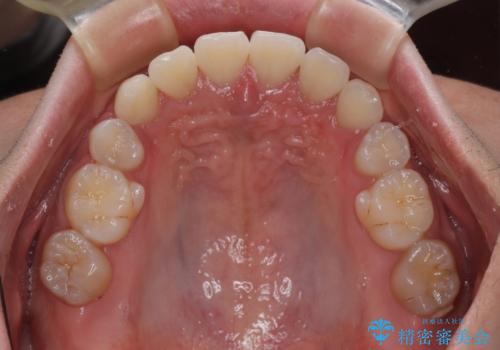

上顎のみの抜歯矯正であったため、治療期間が長期化することが予想されましたが、何とか3年弱の期間で想定通りの仕上がりで終えることができました。